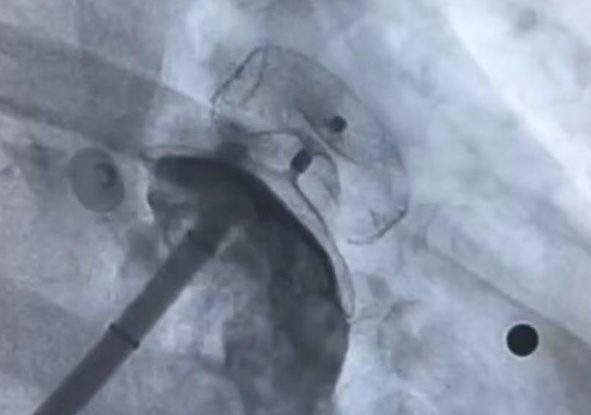

龚辉主任团队慎重考虑,在与患者及家属充分沟通的情况下,决定为患者进行射频消融联合左心耳封堵一站式手术。经过心内科团队近3小时的不懈努力,患者的手术过程十分顺利,有效预防了患者因房颤导致的心源性脑卒中再次发生的可能,也减少了房颤可能导致的心力衰竭。

对于某些不能接受或不宜长时间使用抗凝治疗的房颤患者,医生可能会推荐进行左心耳封堵手术。这是一种微创手术,医生会通过血管将一个特制的封堵器送到左心耳,并在那里展开手术,从而隔离左心耳,防止血栓形成并进入血流。